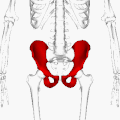

Тазовые кости в скелете таза человека выделены красным